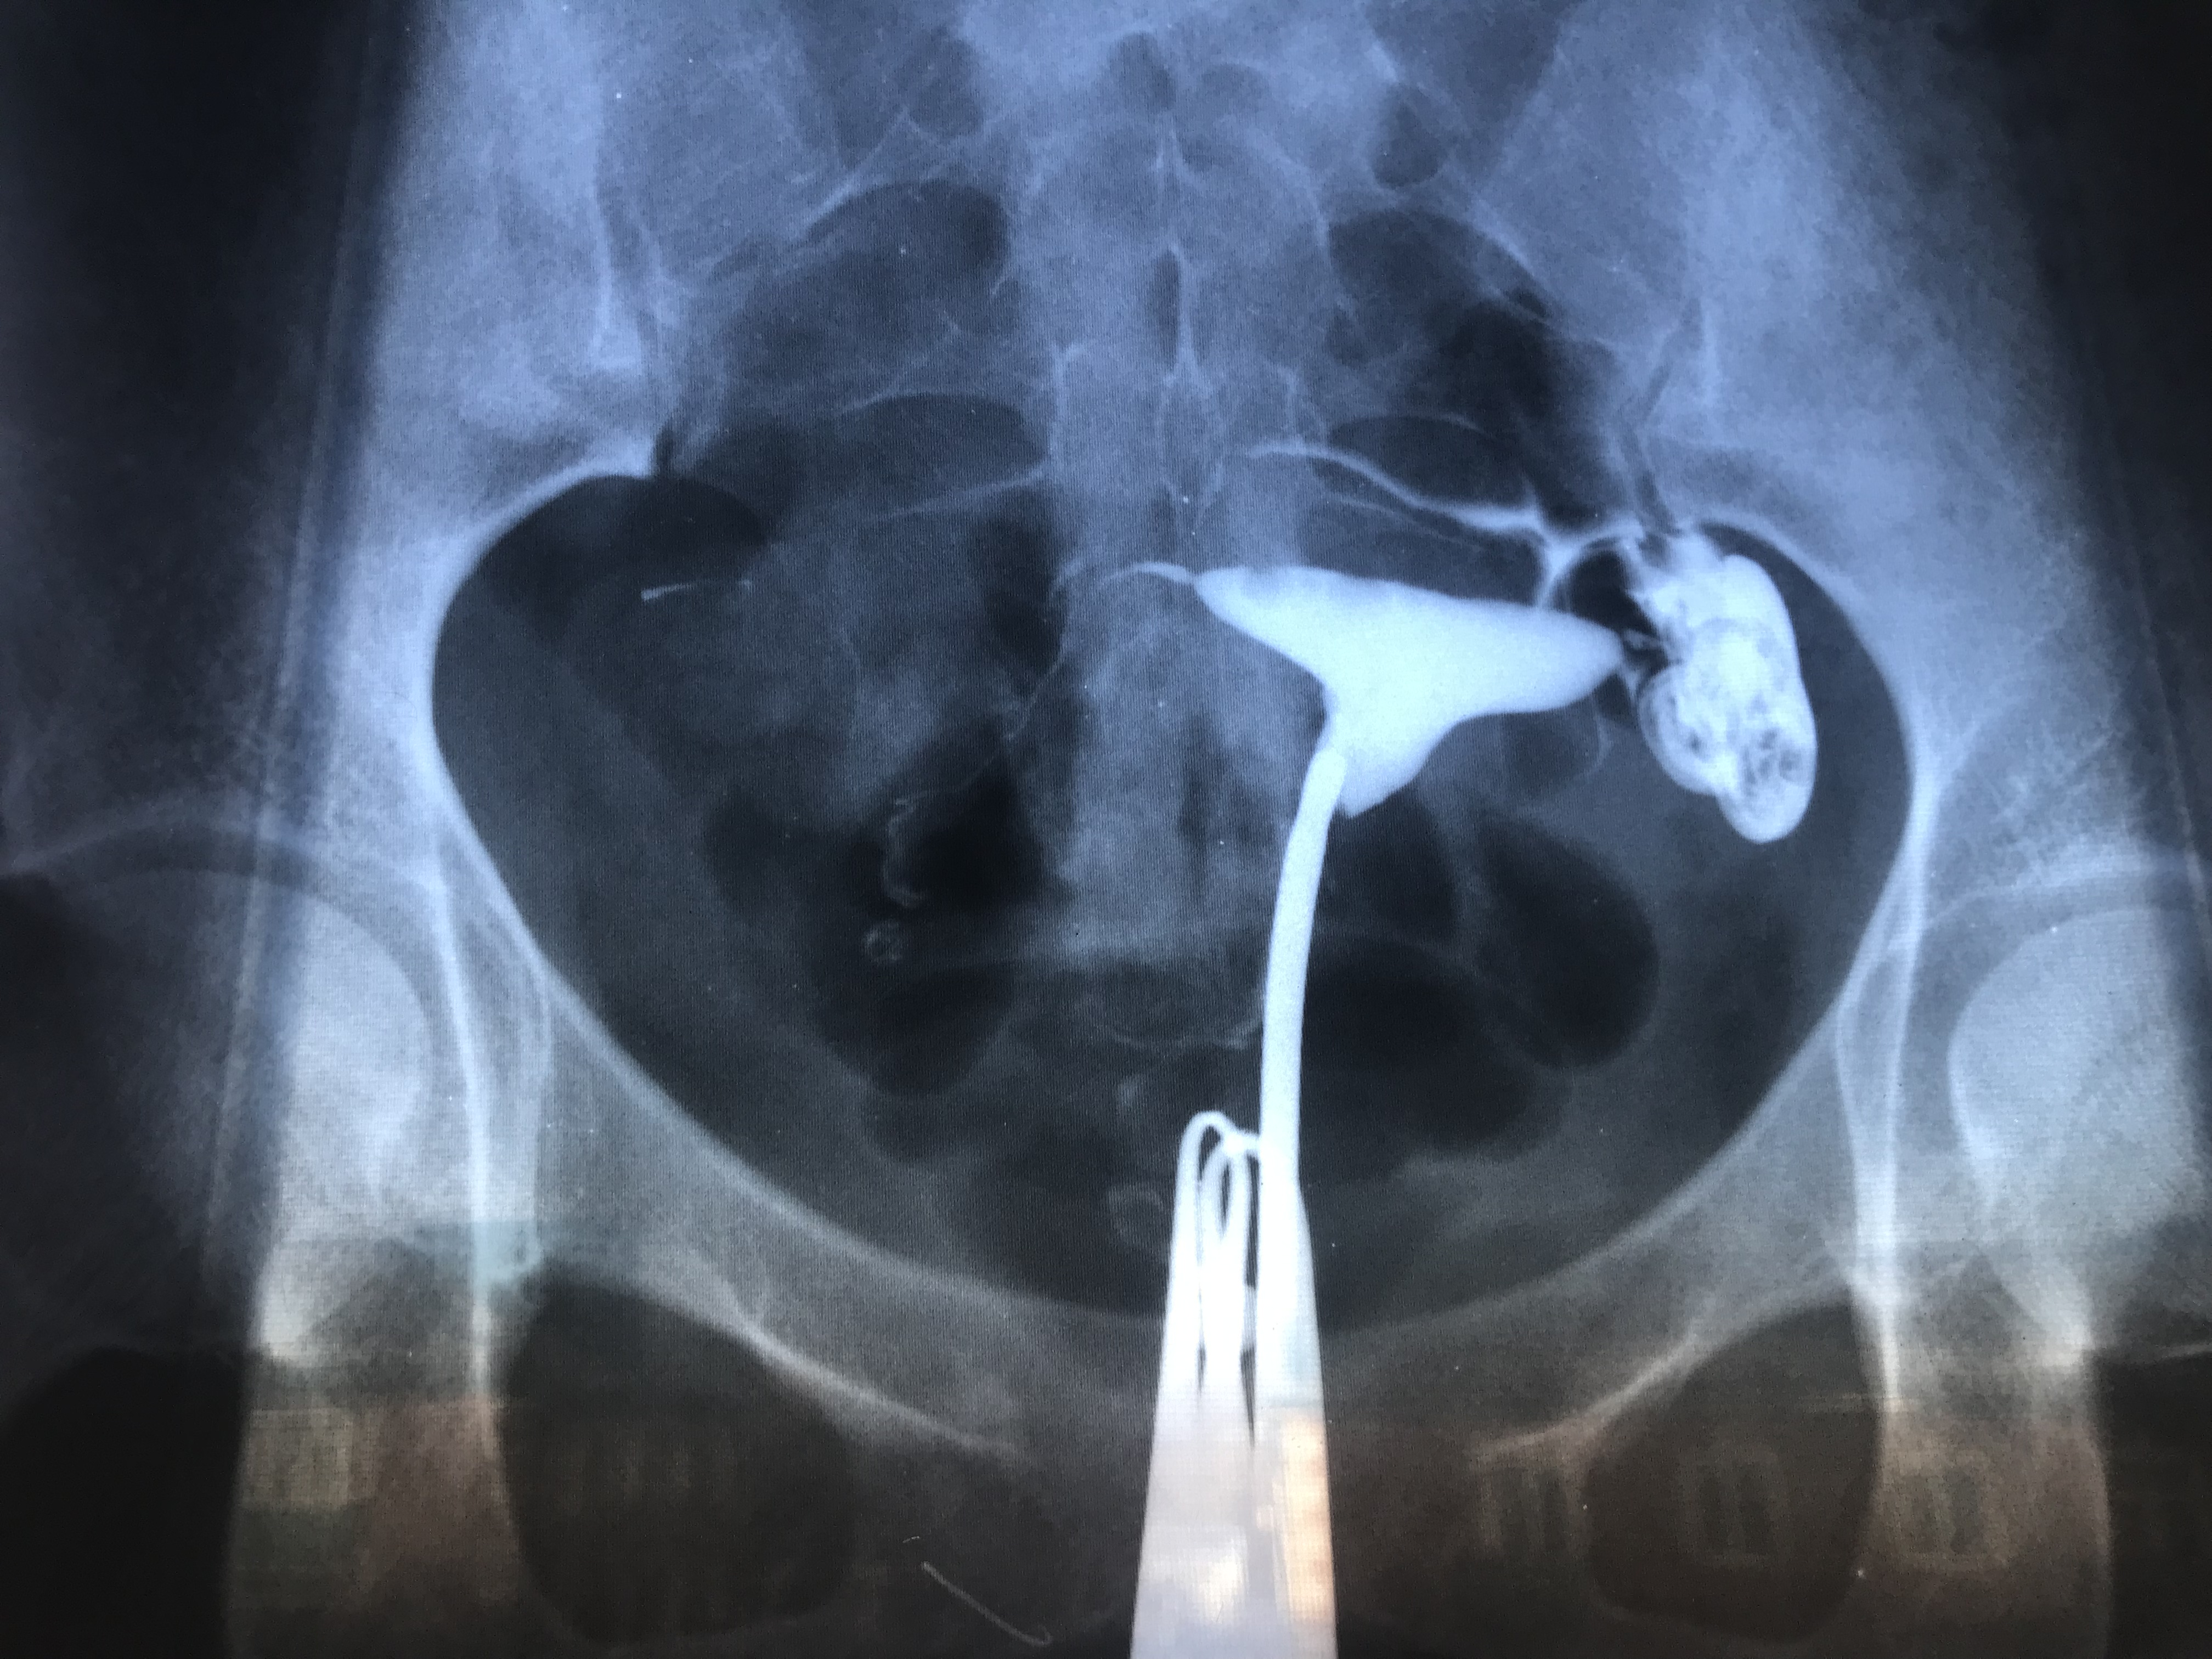

Гистеросальпингография: описание и фотографии